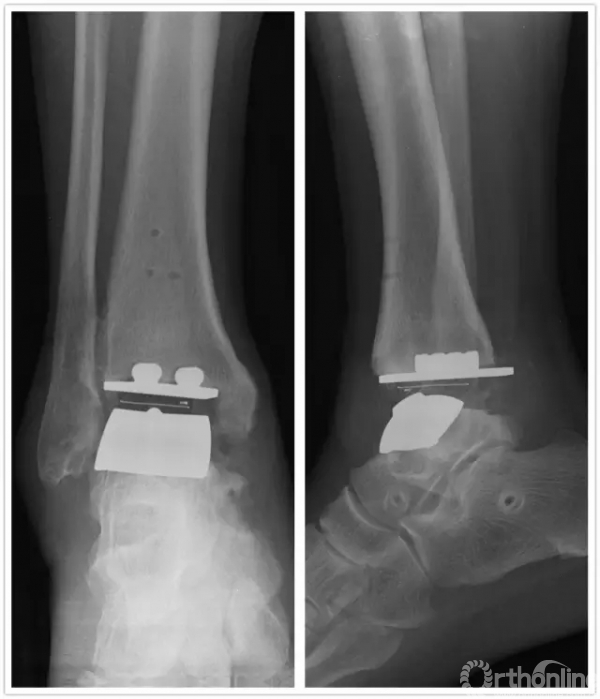

直到1年前,方老伯感觉右侧踝关节又开始出现肿胀疼痛,劳作后加重,最近越来越重。2016年7月再来徐主任门诊复查,徐主任考虑踝关节假体出现了松动,距骨有了塌陷,关节力线有所偏移。鉴于目前瑞金医院足踝外科已经开展踝关节INBONE假体置换术,积累了一定的经验,于是徐主任向患者及家属解释病情,建议再行踝关节翻修术。

手术中首先沿原手术切口进入,保护神经血管肌腱组织,清理踝关节假体周围骨赘,取出原关节假体,将患足置于专门的定制支架中,在透视下反复调整足踝及导针位置,力求最高精确度。在导板的定位下进行胫骨远端和距骨截骨,试样假体大小,置入合适匹配的踝关节假体及垫片完成全踝关节假体的置换,然后再行距下关节融合术。历经4小时,手术过程非常顺利,术后患者恢复良好,手术取得圆满成功。